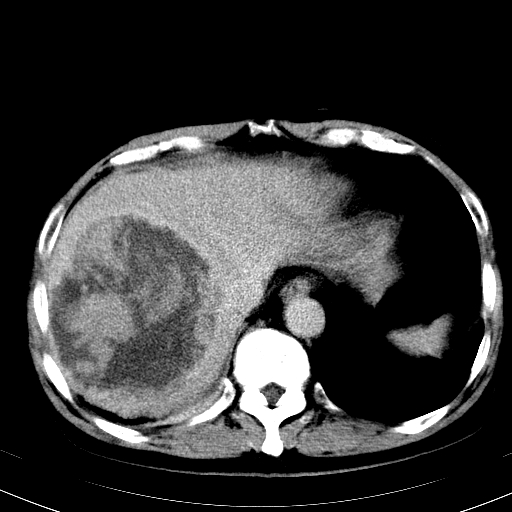

标题: CT14194B:补充延迟期图片

延时期内强化结节明显增多,还是考虑:血管瘤伴坏死 出血!

延迟期的表现不像血管瘤了,但也不支持原发性肝癌。